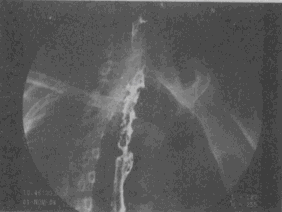

1.男,58岁,进食梗阻感,结合图像,最可能的诊断为

A.正常食管

B.食管静脉曲张

C.食管平滑肌瘤

D.食管上段癌

E.食管下段癌

正确答案:D解题思路:食管范围较长的不规则充盈缺损,管腔变窄,伴表面有龛影,结合病史为食管癌性病变。